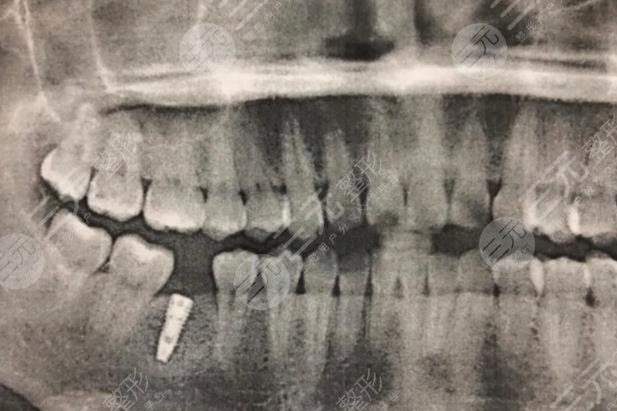

于是我便在后的陪伴下来到这家医院咨询种植牙相关事宜。这里的医生护士果然没让我失望,他们态度较为的好,让人感受不到看牙的恐惧。医生仔细的检查我的牙齿,拍完片以后他跟我分析到我的牙齿虽然龋坏程度较为严重,但是牙周状况较好,无需缓解牙周既可以展开种植牙。,医生根据我的实际情况跟我推荐了,一款合适的材料,综合各方面信息,我接受医生的建议。